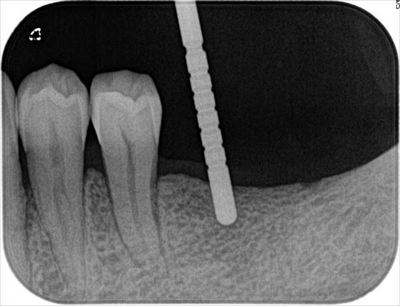

パイロットドリルで確認し、進めます。